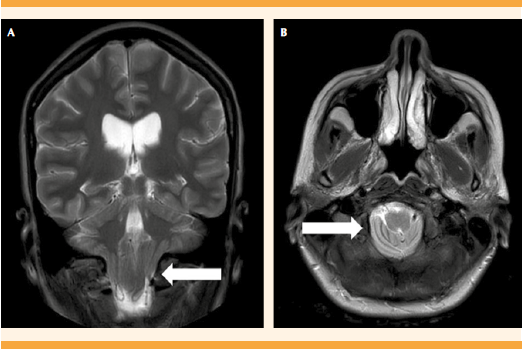

Al examen neurológico la paciente se encontró orientada en persona, tiempo, espacio sin déficit motor o sensitivo, con reflejos osteotendinosos y simétricos en las cuatro extremidades. En la valoración de los pares craneales no hubo déficit ni zonas gatillo que reprodujeran el dolor. Con diagnóstico de cefalea en estudio, con signos de alarma, se hospitalizó para la administración de analgésicos y realización de estudios complementarios. Se formuló el tratamiento analgésico con tramadol y metamizol. Como prueba de bienestar fetal se practicó el perfil biofísico 10-10 y ecografía obstétrica con un peso fetal adecuado para la edad gestacional. La resonancia cerebral reportó el hallazgo de ventriculomegalia supra e infratentorial, sin cambios de migración transependimaria, descenso de amígdalas cerebelosas a través del foramen magno que alcanzaba el nivel del arco posterior de C1, con elongación de los mismos atribuibles a anomalía de Chiari tipo I. Lo anterior confirmó el diagnóstico de cefalea secundaria a malformación de Chiari tipo I. Figuras 1 y 2

Figura 2 Resonancia magnética cerebral secuencia T2; A. Corte sagital con descenso de las amígdalas cerebelosas por debajo del agujero magno (flecha); B. Corte axial con ligero apiñamiento de la médula por el descenso amigdalino (flecha).